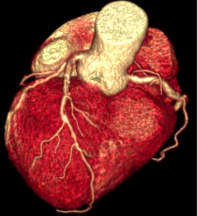

Công nghệ tim mạch Aheart

Phương pháp chỉnh sửa ECG

Khám phá nhiều hơn, đi sâu vào từng chi tiết

Hình ảnh lâm sàng